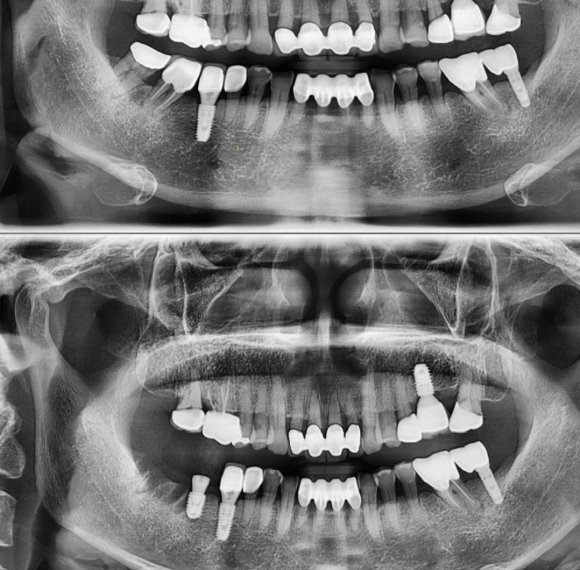

심한 치조 농양을 원인으로 한 어금니 2개 발치 후 1개는 즉시 식립을, 가장 뒤 쪽 1개를 4개월 후 (뼈가 회복된 후) 식립 예정입니다. 임플란트의 계획은 일률적인것이 아닌 임플란트가 심어져야할 부위의 상태에 따라 수술의 시기와 테크닉 그리고 접근 방법이 달라지게 됩니다. #루미니어크라운 #루미네...

심한 치조 농양을 원인으로 한 어금니 2개 발치 후

1개는 즉시 식립을,

가장 뒤 쪽 1개를 4개월 후 (뼈가 회복된 후) 식립 예정입니다.

임플란트의 계획은 일률적인것이 아닌

임플란트가 심어져야할 부위의 상태에 따라

수술의 시기와 테크닉 그리고 접근 방법이 달라지게 됩니다.